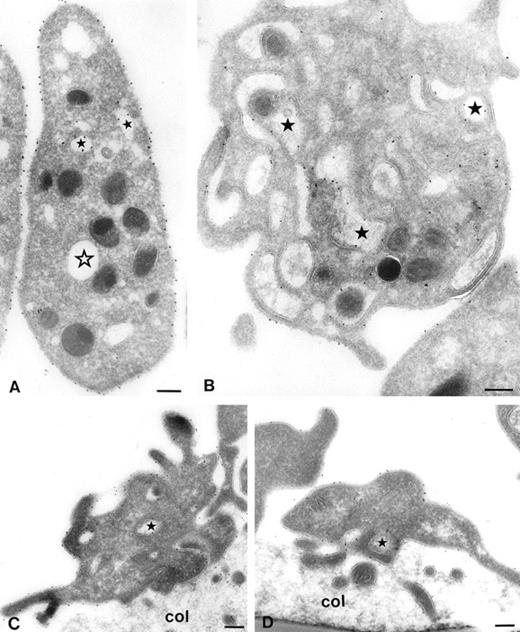

However, it is not clear whether adherent platelets behave identical to platelets in suspension. Once attached to an adhesive surface, it is possible that GPIb, which had disappeared from the platelet surface, becomes mobilized and then participates in platelet adhesion. Therefore immunoelectron microscopic studies were performed. Platelets were stimulated with 15 μmol/L TRAP or vehicle at 37°C. Five minutes after the addition of TRAP, samples were removed for electron microscopy. Immediately thereafter perfusions were started for 5 minutes over collagen type III (shear rate = 1,600 s-1). As shown in Fig 4A, gold particles labeling GPIb are predominantly present on the platelet surface. After stimulation with TRAP, most gold particles are present in the OCS (Fig4B). The relative surface expression of GPIb was quantified by counting the gold particles associated with platelet surface membranes, OCS membranes, α-granules, and undefined structures (Table 2). The percentage of GPIb on the platelet surface of unstimulated platelets was 69.0% ± 2.9% (mean ± SEM, n = 4). After stimulation with TRAP, the percentage of GPIb on the platelet surface was 35.5% ± 2.5% (mean ± SEM, n = 4), representing a 50% decrease in platelet surface GPIb.

Series of electron micrographs showing platelets in suspension (A and B) and adhered platelets to collagen type III (C and D). Whole blood anticoagulated with Orgaran in the presence of dRGDW was stimulated with 15 μmol/L TRAP (B and D) or vehicle (A and C) at 37°C. After 5 minutes, blood samples were drawn, immediately fixed, and used for immunoelectron microscopy (A and B), and perfusions were started for 5 minutes at a shear rate of 1,600 s-1 over coverslips coated with collagen type III. Perfused coverslips were also immediately fixed and used for immunoelectron microscopy (C and D). Immunolabeling was performed on frozen thin sections with MoAb AK3 and 10 nm protein-A gold. Closed stars represent the OCS with gold particles. Open star represents OCS without gold particles. Col, collagen. Bar, 200 nm.

After platelet adhesion to collagen type III, GPIb was redistributed to the platelet surface. Both TRAP-stimulated and nonstimulated adhering platelets showed pronounced cell surface ruffling (ie, pseudopod formation) (Fig 4C and D). As shown in Table 2, the percentage of GPIb on the platelet surface of vehicle-treated platelets was 64.4% ± 3.7% (mean ± SEM, n = 3). The percentage of GPIb on the platelet surface of TRAP-treated platelets was 62.0% ± 4.5% (mean ± SEM, n = 4), which was not significantly different from vehicle-treated platelets. In a parallel flow cytometric experiment, we observed that the surface expression of GPIb on TRAP-stimulated platelets present in the perfusate after perfusion was still reduced (data not shown). This means that GPIb rapidly redistribute to the platelet surface on adhered TRAP-stimulated platelets, but not on TRAP-stimulated platelets in suspension. The perfusion process by itself did not influence the time-dependent return of GPIb to the platelet surface in circulating platelets.